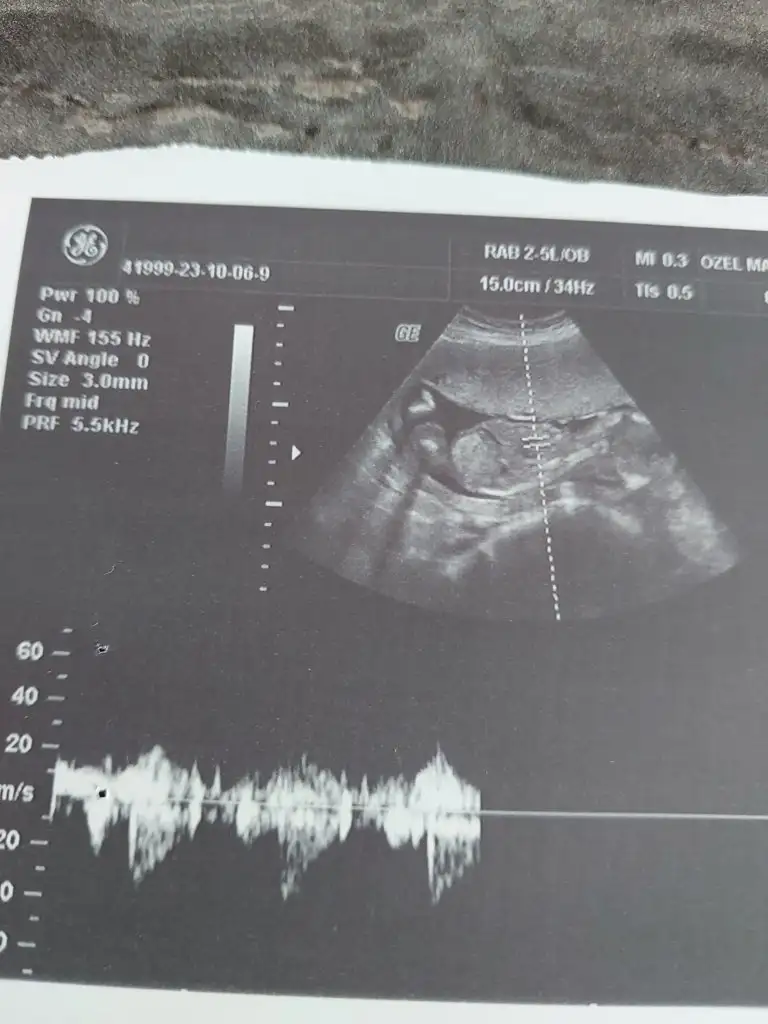

merhaba bize de bakabilir misiniz ? Herkes erkeğe benzetiyor ama gönlümden kız geçiyor ultrason biraz net değil